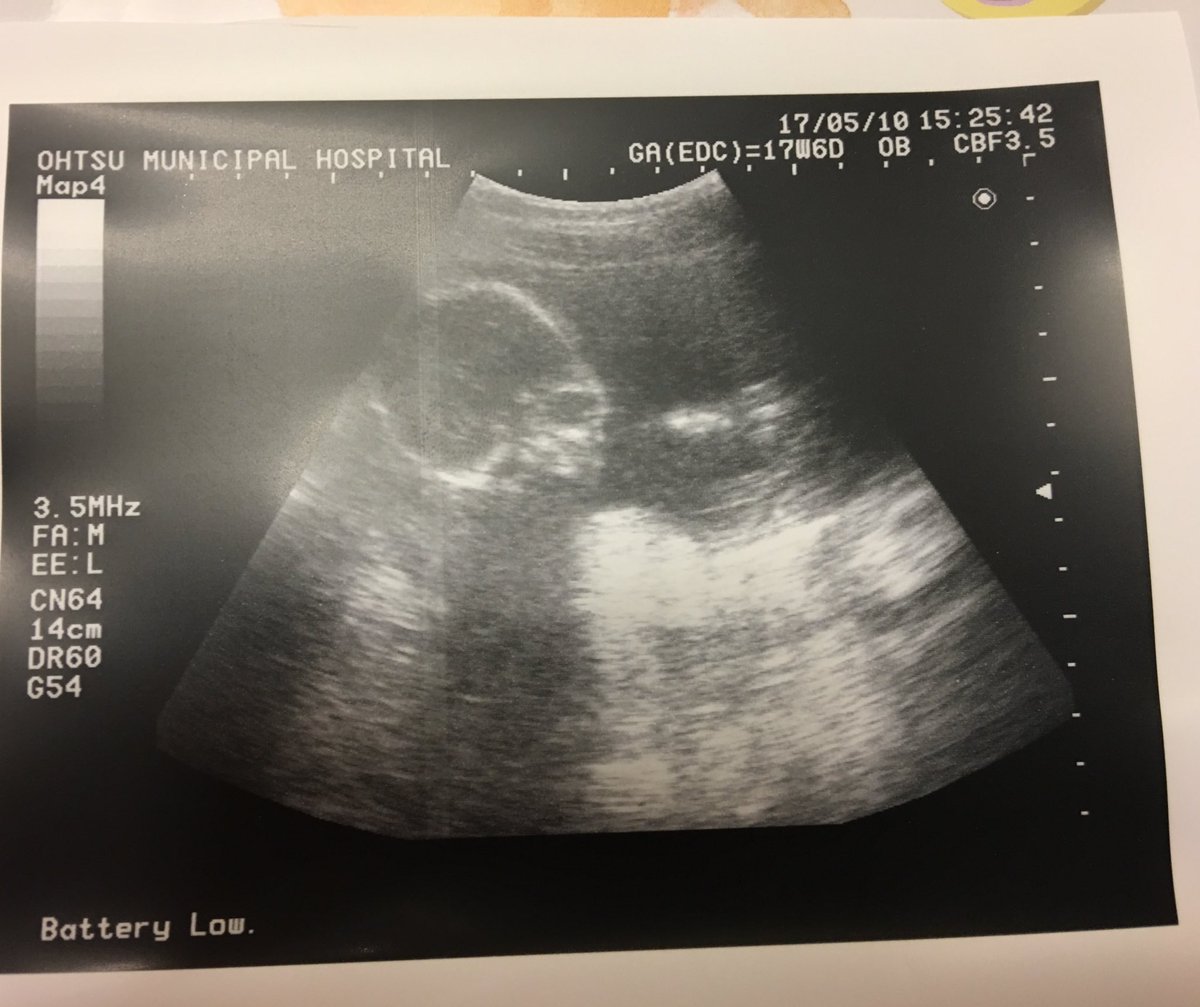

4ヶ月頃男の子と言われ、見せてもらったエコー写真には しっかりとおまたの間に突起物が。 でもその後女の子に修正され、出てきた赤ちゃんは女の子でした。 15週くらいって、女の子でも突起物があるようですよ。 参考urlにエコー写真が載ってます。. 妊娠 正面からのエコー写真、男の子? 初めまして、エコー写真について質問させてください。 妊娠17週目の時のエコー写真です。性別を聞いた際に先生がなにが突起物のような物が見える気がしたけどへその 質問No. 男の子のエコー写真 へその緒が、股にずっと挟まった状態だったのか、 手を股に置く癖があったのではないか、と言われたそうです。 q 22週目エコー写真.

妊娠 正面からのエコー写真、男の子? 初めまして、エコー写真について質問させてください。 妊娠17週目の時のエコー写真です。性別を聞いた際に先生がなにが突起物のような物が見える気がしたけどへその 質問No. エコー写真での性別の見分け方について エコー写真で性別を見分けることができます。 赤ちゃんは、だいたい9週目頃に入るとだんだんと男の子、女の子として変化を始めていきます。 ただ、9週目頃では赤ちゃんが小さいため性別の判断はつきません。. 医師はどこを見て性別を判断しているのか? 医師はエコー写真のどこを見て、性別を判断しているのかというと、 赤ちゃんの足と足の間、股間部を見て主に男の子か女の子かを判断しています。 これは男女で最も違いのある部分なので、ここを確認すればすぐに結果がわかります。.

17週のときのエコーです これは男の子のシンボルでしょうか それとも 妊娠 教えて Goo